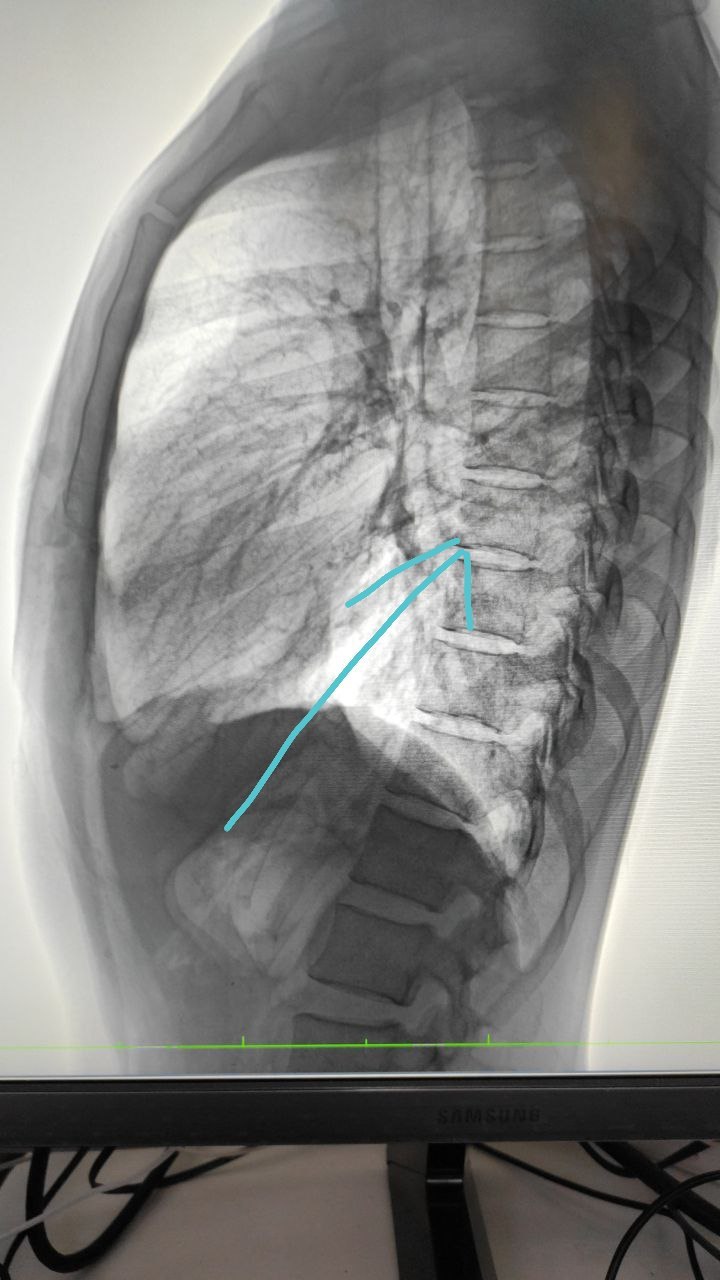

Женщина 38 лет

Флюорообследование

Слева округлой тень на прямой проекции в боковом я не видел как думаете?